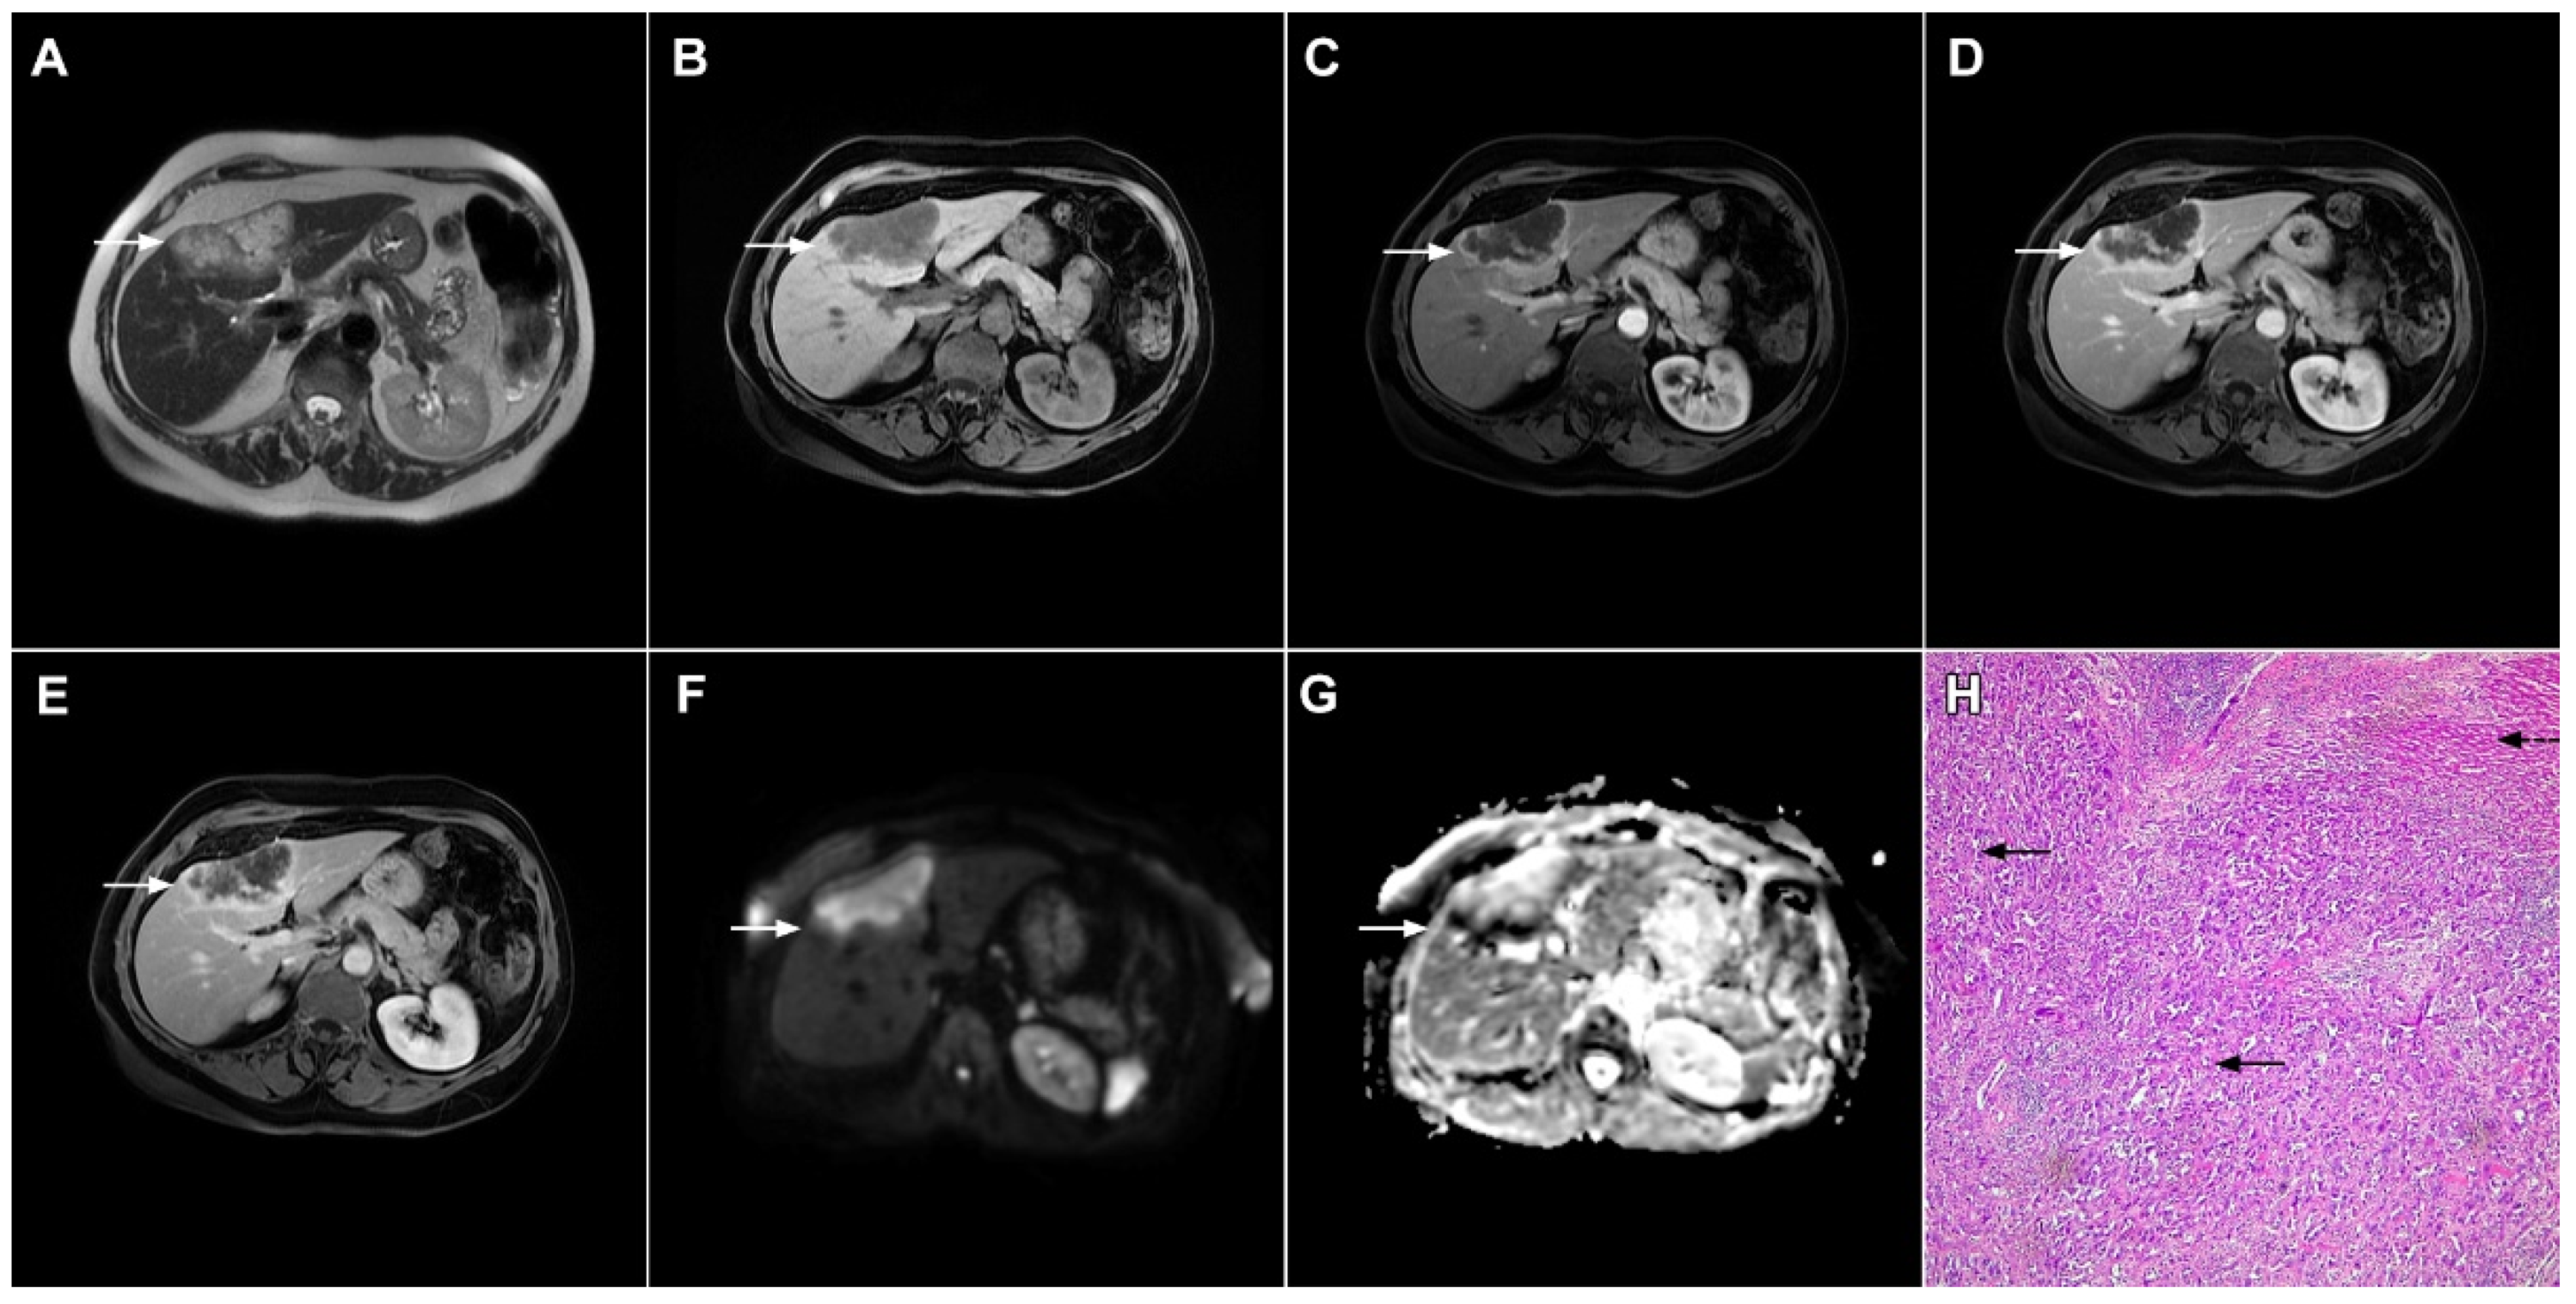

2.1. Typical Imaging Features of mICC

2.2. Atypical Imaging Features of mICC

3.1.1. Focal Confluent Fibrosis

3.1.2. Sclerosing Hemangioma

3.1.3. Inflammatory Pseudotumor

3.1.4. Pyogenic Liver Abscess